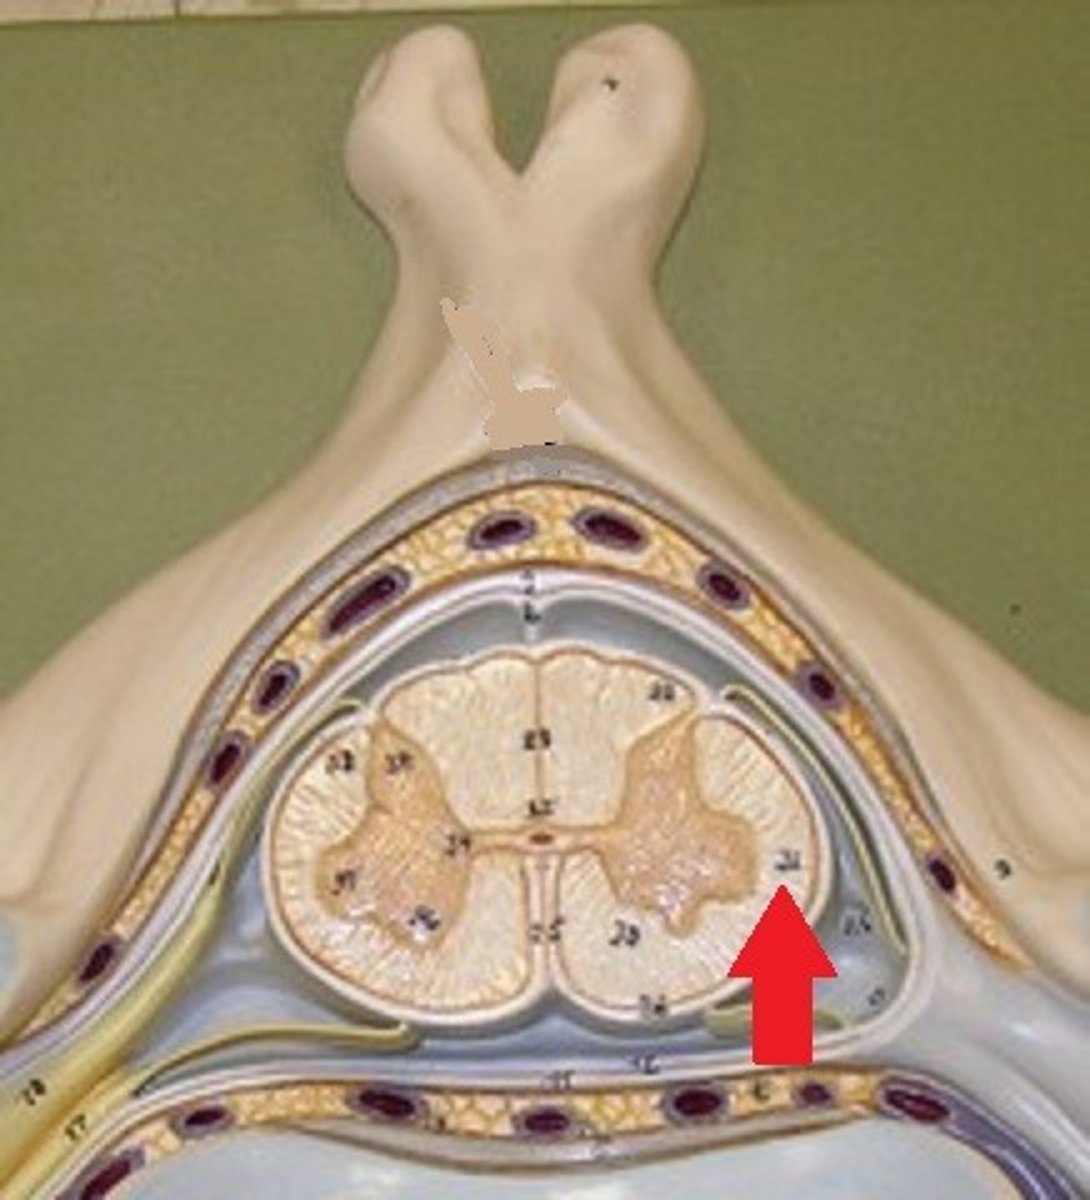

posterior white column

Sends information up to the brain

sensory info

lateral white column

Information descends from the brain

anterior white column

Information descends from the brain (Brings info back to the spinal cord)

motor commands

spinal meninges

3 specialized membranes surrounding spinal cord and brain

Stability, shock absorption, carry blood supply (oxygen and nutrients)

3 spinal meninges (Superficial to deep)

dura mater, arachnoid mater, pia mater

Dura mater

tough outer layer of the meninges

arachnoid mater

Made of simple squamous epithelium

Pia mater

thin, delicate inner membrane of the meninges

subarachnoid space

between arachnoid mater and pia mater

filled with cerebrospinal fluid

shock absorber; diffusion of gases, nutrients, etc.

blood vessels for spinal cord

epidural space